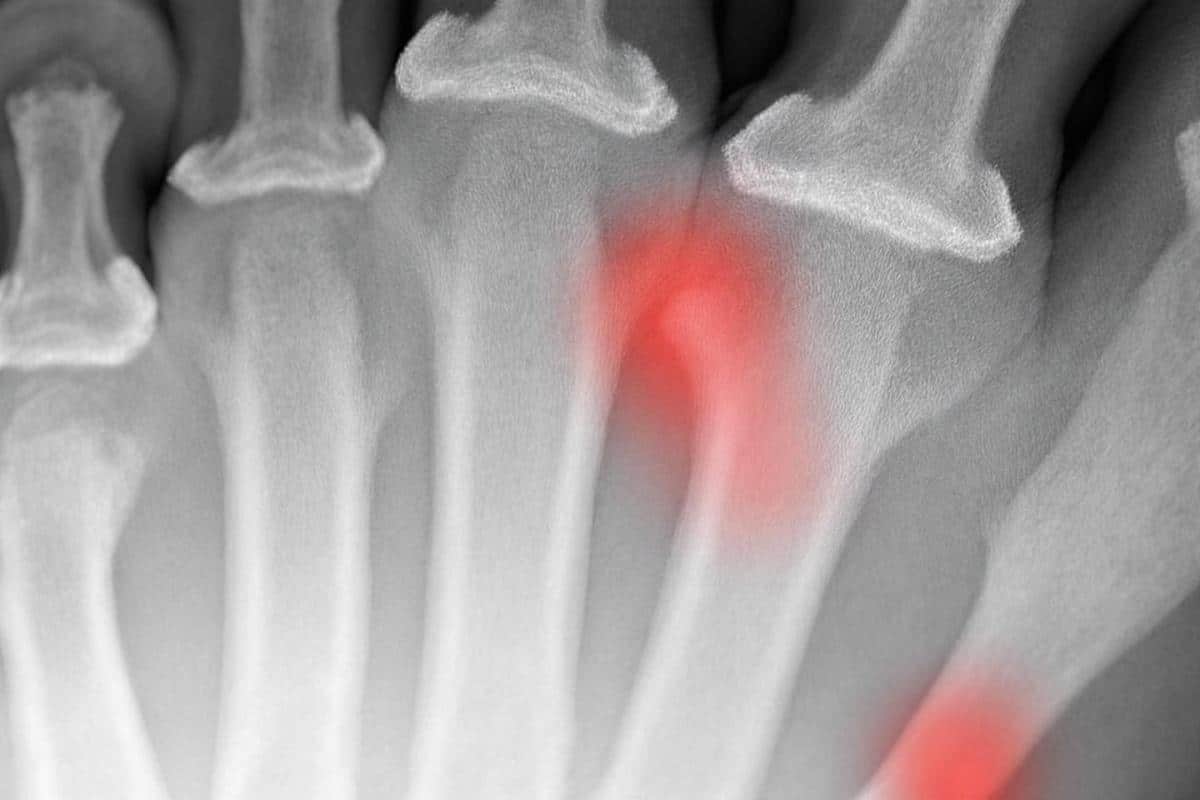

Le cinquième métatarsien peut se fracturer à différents endroits, chaque localisation présentant des spécificités importantes pour la durée de consolidation osseuse. La fracture par avulsion, située au niveau de l’apophyse styloïde à la base de l’os, survient lorsque le tendon du muscle court fibulaire exerce une traction excessive. Cette forme présente généralement un pronostic favorable avec une guérison entre quatre et huit semaines.

La fracture de Jones se localise à la jonction entre la métaphyse et la diaphyse, environ quinze millimètres après la base. Cette zone particulière pose problème car elle bénéficie d’une vascularisation limitée, ce qui augmente considérablement le risque de pseudarthrose ou de retard de consolidation. Pour cette raison, la durée de guérison s’étend généralement entre huit et douze semaines, avec une moyenne de trois mois pour obtenir une consolidation complète.

Les fractures de stress, également appelées fractures de fatigue, apparaissent sans traumatisme violent. Elles résultent d’une activité physique intense et répétée qui soumet l’os à des contraintes excessives. Ces lésions nécessitent fréquemment une période de récupération prolongée pouvant atteindre douze à vingt-quatre semaines. Enfin, les fractures diaphysaires touchent la partie centrale de l’os lors de chocs directs et peuvent présenter des complications nécessitant parfois une intervention chirurgicale.